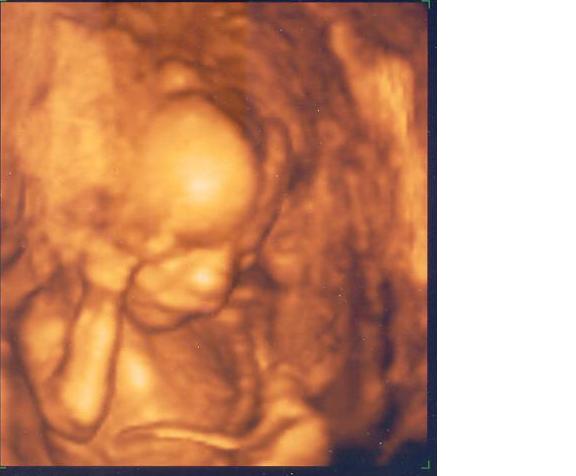

Kicsit eltüntem, de most itt vagyok :) Anno ígértem képet is 17. hetes Mociról, most megpróbálom feltölteni...

[b]Mumigugo, Tigris, üdv a fiús anyukák klubjában :D Én az elejétől éreztem hogy fiú lesz...Mi az András nevet választottuk (több oknál fogva, egypár : férjem 2.neve, férjem Apukája neve és ahány Andrást ismerek, mind jó fej :lol:

Mocinak is keresztbe volt téve a lába, de attól még a kis kukkantyú látható volt, elég egyértelműen :D A 20. héten (köv. kedd) megint megyünk dokihoz, akkor fogunk csináltatni mi is 4D-s felvételt.

András alias Moci Kép Moci alias András [/img]

Egyébként, amikor kértem képet a dokitól, nem is gondoltam hogy 3D-s lesz, és amikor megláttuk...hát gondolhatjátok milyen érzés volt :D